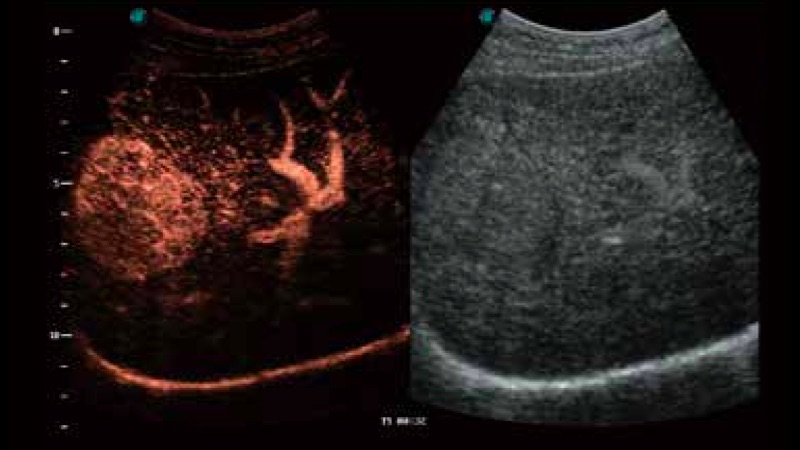

造影成像

造影成像功能和定量分析工具包使医生能够更好的评估血流灌注情况。独特的动态声压控技术有效控制造影剂的声压,保证更长的造影剂持续时间,更好的观察病变灌注的延迟相位。

S-Live 高分辨率容积成像

通过仿真成像技术对3D/4D立体数据进行渲染,多种初始光源位置可选,并支持轨迹球360°光源位置自由调节,清晰显示不同方位容积图像细节。

临床图像